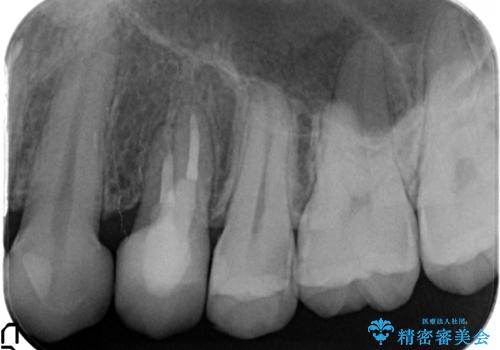

左上4の補綴物を除去したところ縁下歯質だったため、歯牙の挺出を提案し行いました。

挺出終了後は歯肉切除および骨外科により歯周組織を整え、オールセラミッククラウンによる補綴を行いました。